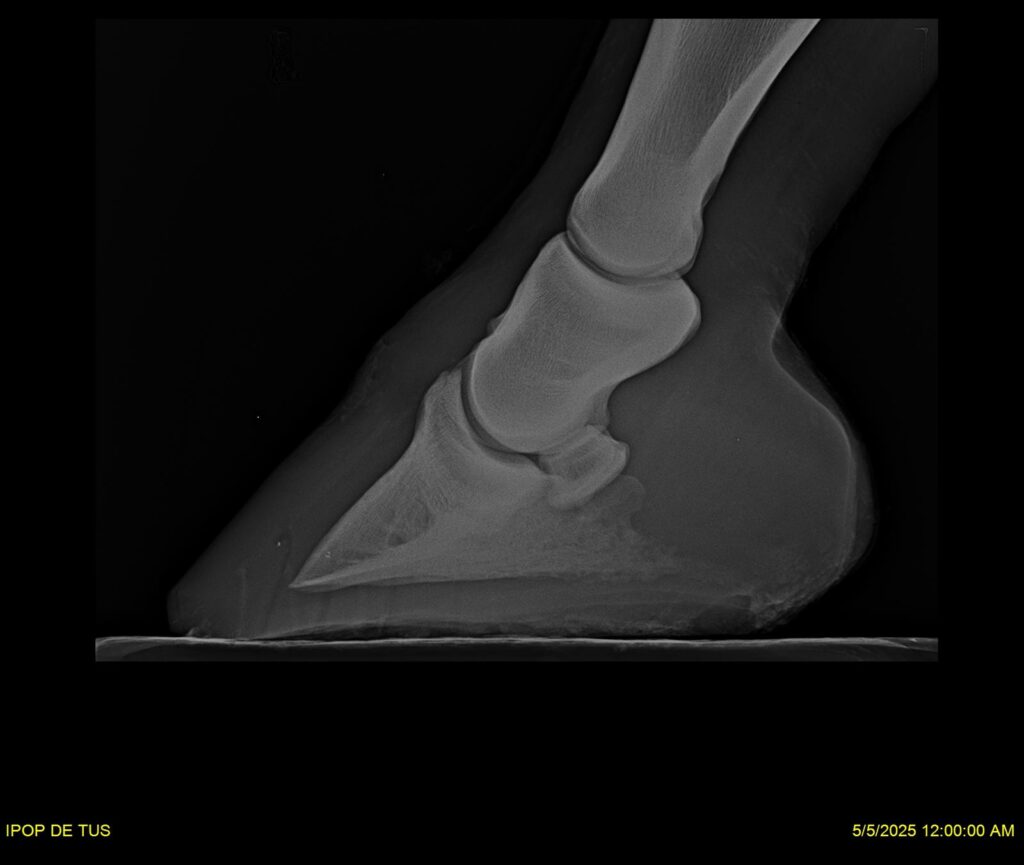

IPOP DE TUS, selle français, hongre, prendra 8 ans en 2026. LIFESTYLE x EROTICBLUS MONTOIS. Sans faute sur 125 et 130. Gentil cheval, respectueux avec des moyens et de la force. Transport OK, maréchalerie OK (pieds nus), santé RAS, Bilan clichés radios + clinique OK.

RADIOS ET CLINIQUE